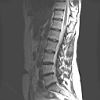

Lage Wervel Zuil